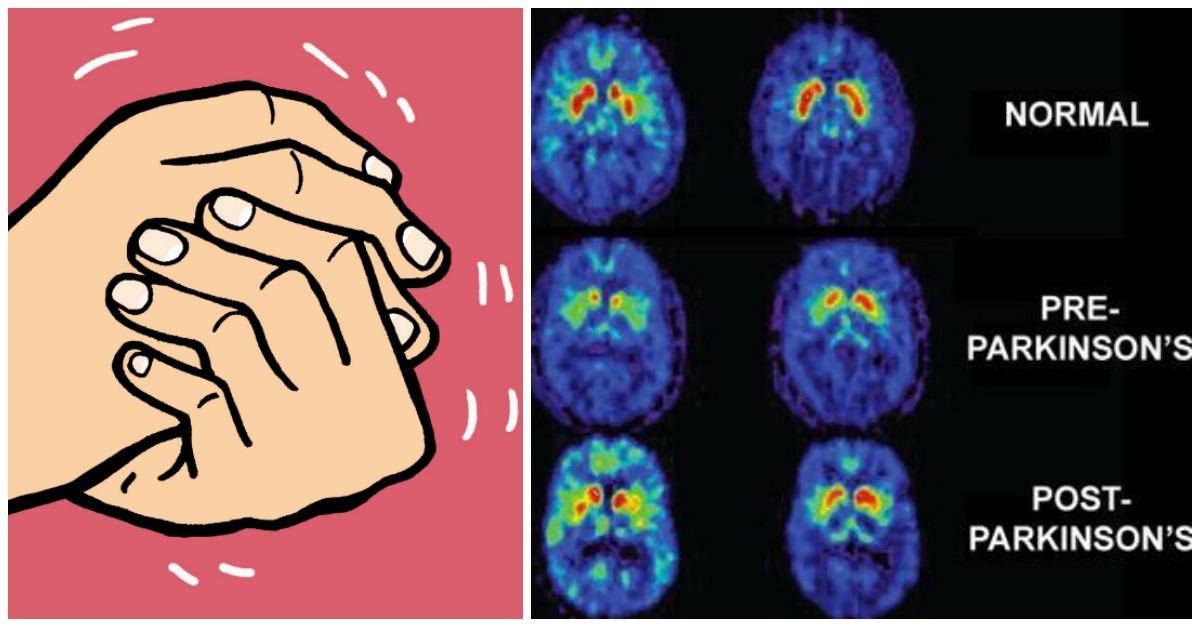

Fino a poco tempo fa, il Parkinson era stato pensato come una malattia che inizia nel cervello, distruggendo i centri di movimento e causando tremori e perdita di movimento. Una nuova ricerca pubblicata questa settimana sulla rivista Brain, mostra che la mutazione genetica più comune del Parkinson può cambiare il modo in cui le cellule immunitarie reagiscono a infezioni generiche come il raffreddore, che a loro volta innescano la reazione infiammatoria nel cervello che causa il Parkinson. La ricerca offre una nuova comprensione della malattia di Parkinson.

“Sappiamo che le cellule del cervello chiamate microglia causano l’infiammazione che alla fine distrugge l’area del cervello responsabile del movimento nel Parkinson”, ha detto Richard Smeyne,Direttore del Jefferson Comprehensive Parkinson’s Disease and Movement Disorder Center presso l’ Istituto Vickie e Jack Farber per Neuroscienze . “Ma non era chiaro come una mutazione ereditaria comune fosse coinvolta in quel processo e se la mutazione alterasse la microglia”.

Nonostante il fatto che LPS non ha attraversato la barriera emato-encefalica, i ricercatori hanno dimostrato che le citochine elevate erano in grado di entrare nel cervello, creando un ambiente che causava l’attivazione patologica della microglia e distruggeva la regione del cervello coinvolta nel movimento.